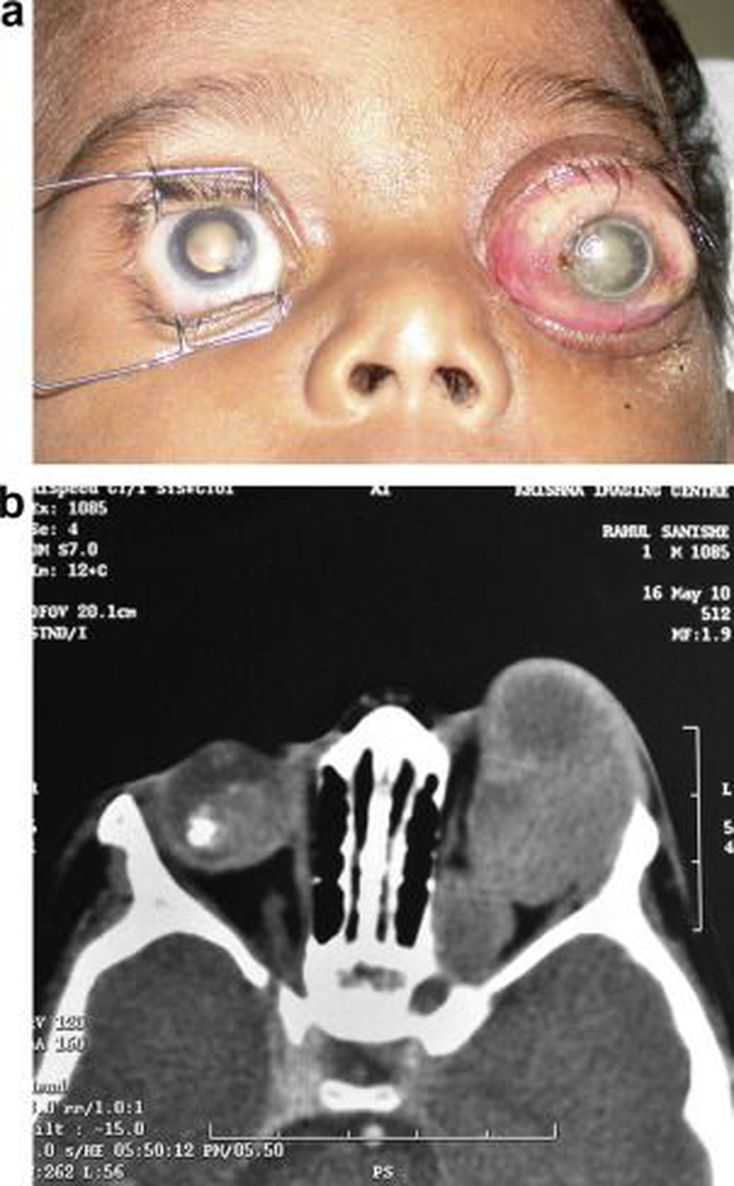

Retinoblastoma is a common ocular malignancy of childhood. The initial presentation is leukocoria or white eye reflex. While the normal eye reflects red light, an eye with retinoblastoma or any other opacity will reflect white light instead. If not treated in time, it invades and leads to significant proptosis. There may be accompanying cellulitis, tumor necrosis or eyelid swelling. Source: https://www.sciencedirect.com/science/article/pii/S1319453410001086